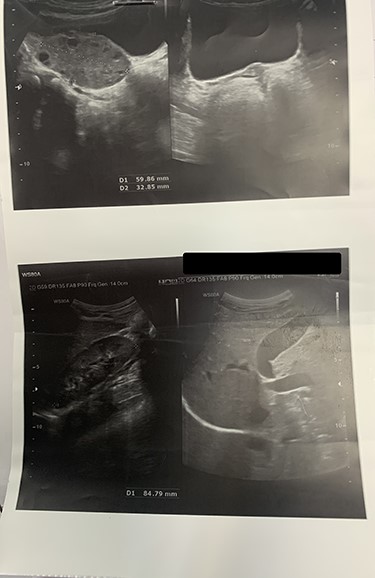

On laboratory data, the WBC count was 11500/mm3. Other exams were unremarkable. To rule-out the diagnosis of appendicitis, ultrasonography was done that revealed torsion of the left ovary with minimal free fluid in the pelvis. Importantly, the radiologist could not observe the uterus and right ovary. Other organs such as the liver, gall-bladder, both kidneys and bladder were reported normal (Fig 1).

Ultrasonography shows the enlargement of the right ovary in size of 59 × 32 mm with increased stroma vulnerable of ovarian torsion. Uterus and the left ovary cannot be seen.